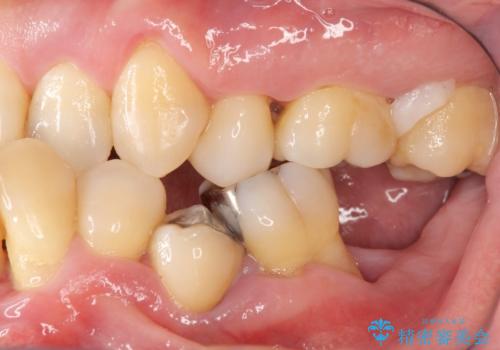

インプラント治療を併用した全顎歯周病治療

- 「仕事のリタイヤに目処がつき、今後は自分の健康にお金をかけたい。しっかりと食事ができる口腔内環境にしてほしい。」と全体的な治療を希望され来院されました。

全体的に重度の歯周病が認められ、抜歯が必要な部位はインプラント治療を、残すことのできる歯には再生治療を含めた歯周病治療を行い全体的な治療を進めてきます。